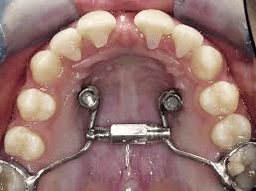

Mini Screw Assisted Treatment

Advanced orthodontic technique using temporary anchorage devices (TADs) to achieve complex tooth movements that were previously difficult or impossible. Mini screws provide stable anchorage without relying on patient compliance.

Key Benefits

Precise Tooth Movement

Faster Treatment Time

Minimal Patient Cooperation Needed

Correction of Complex Cases

Temporary Anchorage

Minimally Invasive Procedure